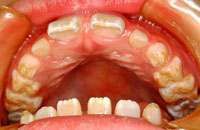

時々、保健センターの1歳半児検診で、虫歯を見て「これは形成不全」といわれ、直す必要はないですよ、といわれる患者さんがいるようです。「形成不全症」というのは遺伝性の病気で、エナメル質、または象牙質の元となる細胞がうまく作られなかったものです。お口中の全部の歯が茶色っぽくなったり白っぽくなったりします(右上下写真)。

検診した方が言いたかったのは「減形成」のことでしょう。減形成はエナメル質ができる(カルシウムが沈着して硬くなる)時の異常で、一本の歯、またはお口の中の一部の歯に起こります。原因はいくつかあります。

乳歯の場合はお母さんのおなかの中にいる時にエナメル質が硬くなりますから、お母さんの体が不調だった時期に対応して部分的に左右対称に茶色くなります。歯の表だけとか裏だけとか右の歯だけ茶色くなることはありません。

永久歯の場合ですが、先行する乳歯の異常に関係するものがほとんどです。その下にある永久歯が作られる時期にぶつけたり、進行した虫歯のために根の先に膿がたまった状態が続いていたりすると、エナメル質がうまく作られず、その時期に対応した部分が茶色くなります(右写真)。

下の写真のように歯の外側だけ、左右非対称の場所に茶色い穴が開いているのはやはり虫歯です。